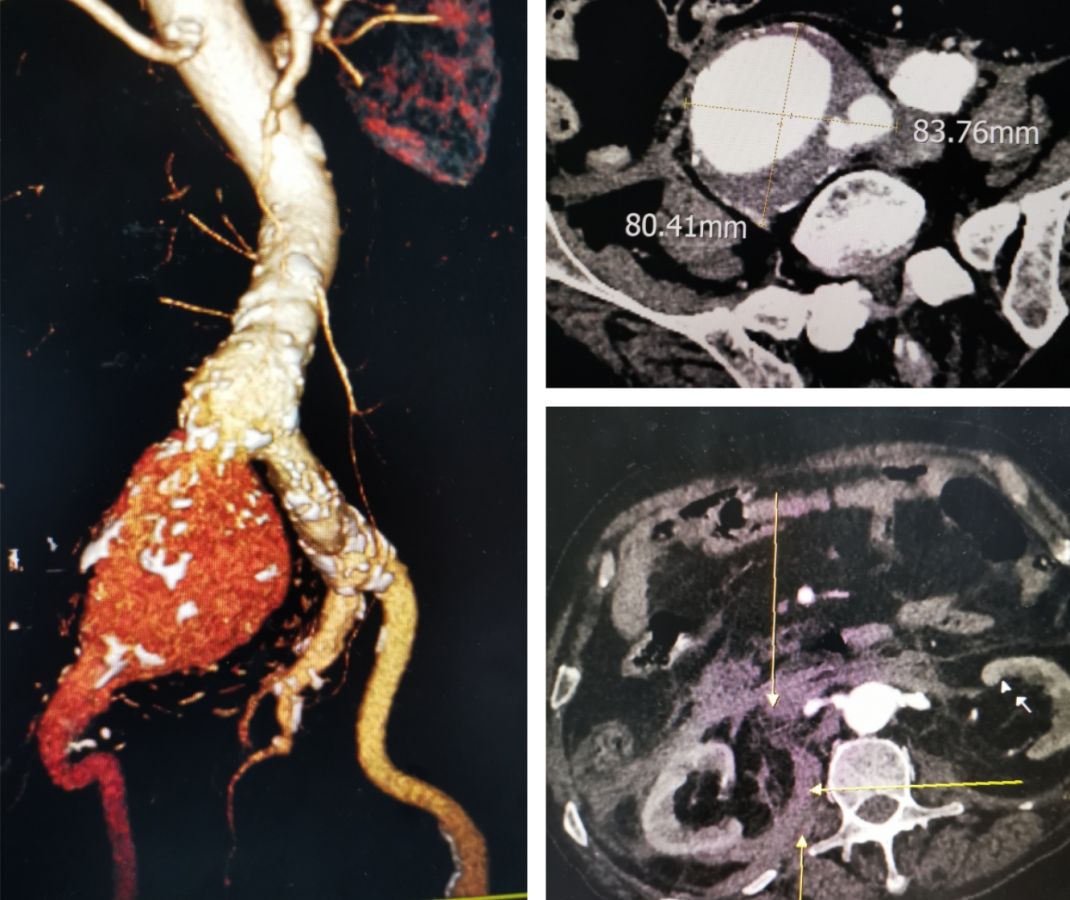

半岛网2月20日讯(记者 张家瑞)83mm巨大髂总动脉瘤完全破裂,血压断崖式下降,心脏濒临停跳。八旬老兵,命悬一线,“我们愿意搏一搏!”家属的信任如同医生与死神抢人的决心一样的坚定,青岛市市立医院多学科协作,抢救“火力全开”,紧急微创手术,拆除破裂的“血管炸弹”。

图释:右髂总动脉瘤直径达83mm,破裂后渗血蔓延至肾水平